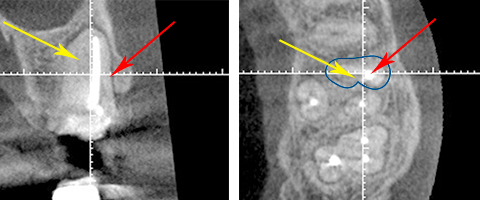

大阪の根管治療の専門の先生がこの方法を発明しまして、以下の写真の様にマイナスドライバーを2本使ってテコの原理を用い金属の土台を除去します。

80%以上この方法で金属の土台は除去することが可能です。

歯を全く削らず、しかも短時間で出来るのです。症例にもよりますが、だいたい数分でできます。以前の様に地味ーに削っていく方法だと20分以上かかったものです。